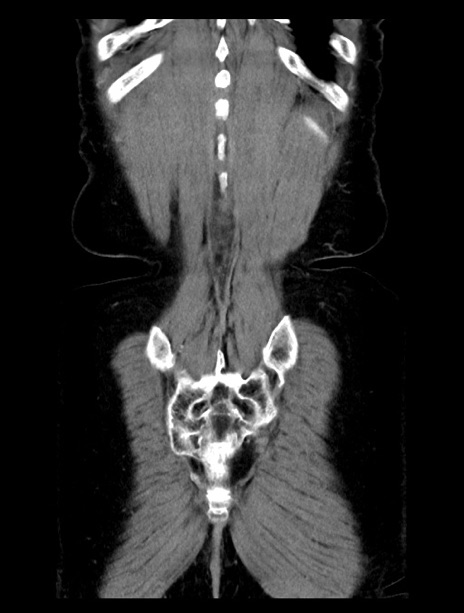

症例23(冠状断像)

【症例】70歳代女性

【主訴】下腹部痛・嘔吐

【現病歴】2日前より腹痛あり。昨日嘔吐あり。症状改善しないため来院。

【既往歴】胃GISTに対して胃部分切除後。

【身体所見】BT 37.1℃、BP 128/77mmHg、腹部:平坦・軟、下腹部に圧痛あり。

【データ】WBC 10200、CRP 0.31